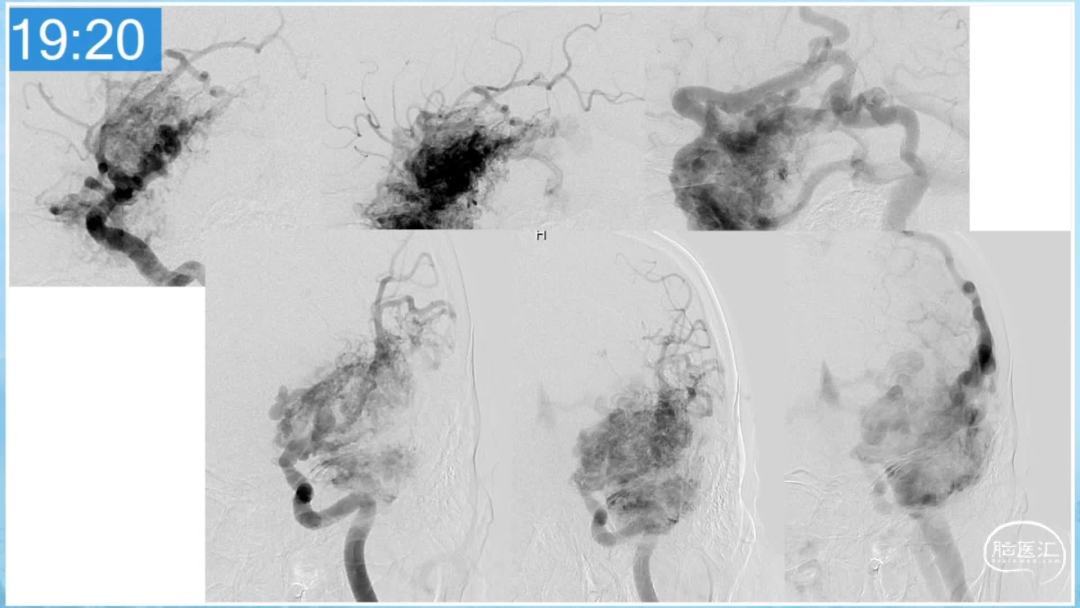

本期为大家特别分享:空军军医大学唐都医院邓剑平教授的精彩会议内容《颅内动静脉畸形的复合手术治疗》,欢迎大家阅读和分享!

合理的复合平台下的综合治疗,针对每一个病变对应不同方法安全性分析,不预设、不排斥,每种技术发挥到最佳,互相保障。